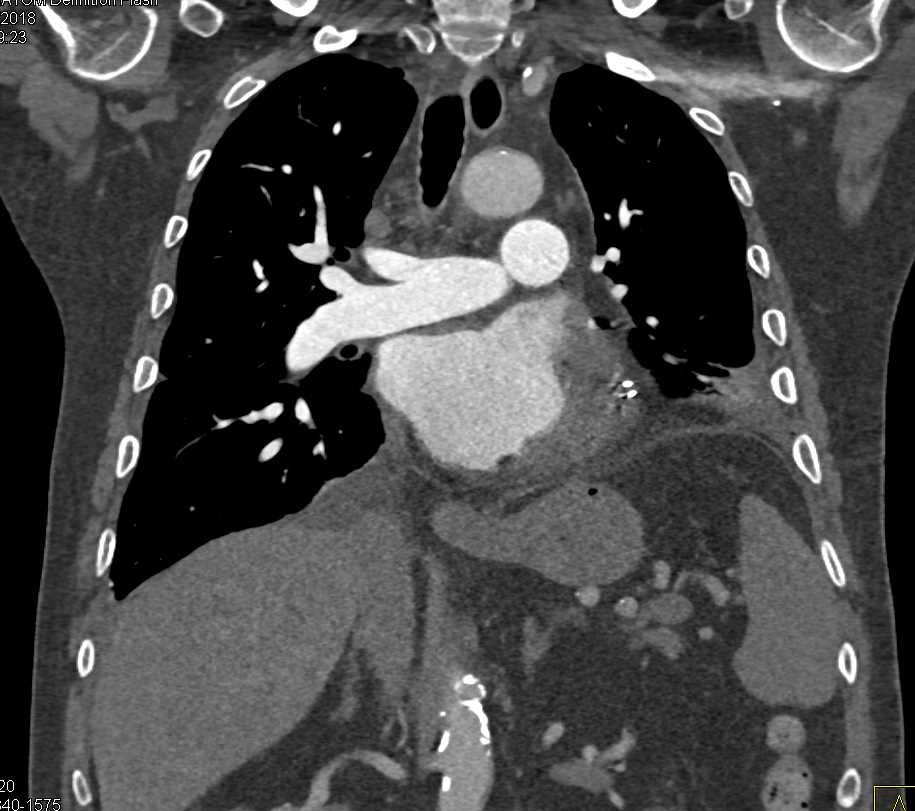

Post Cardiac Surgery Changes